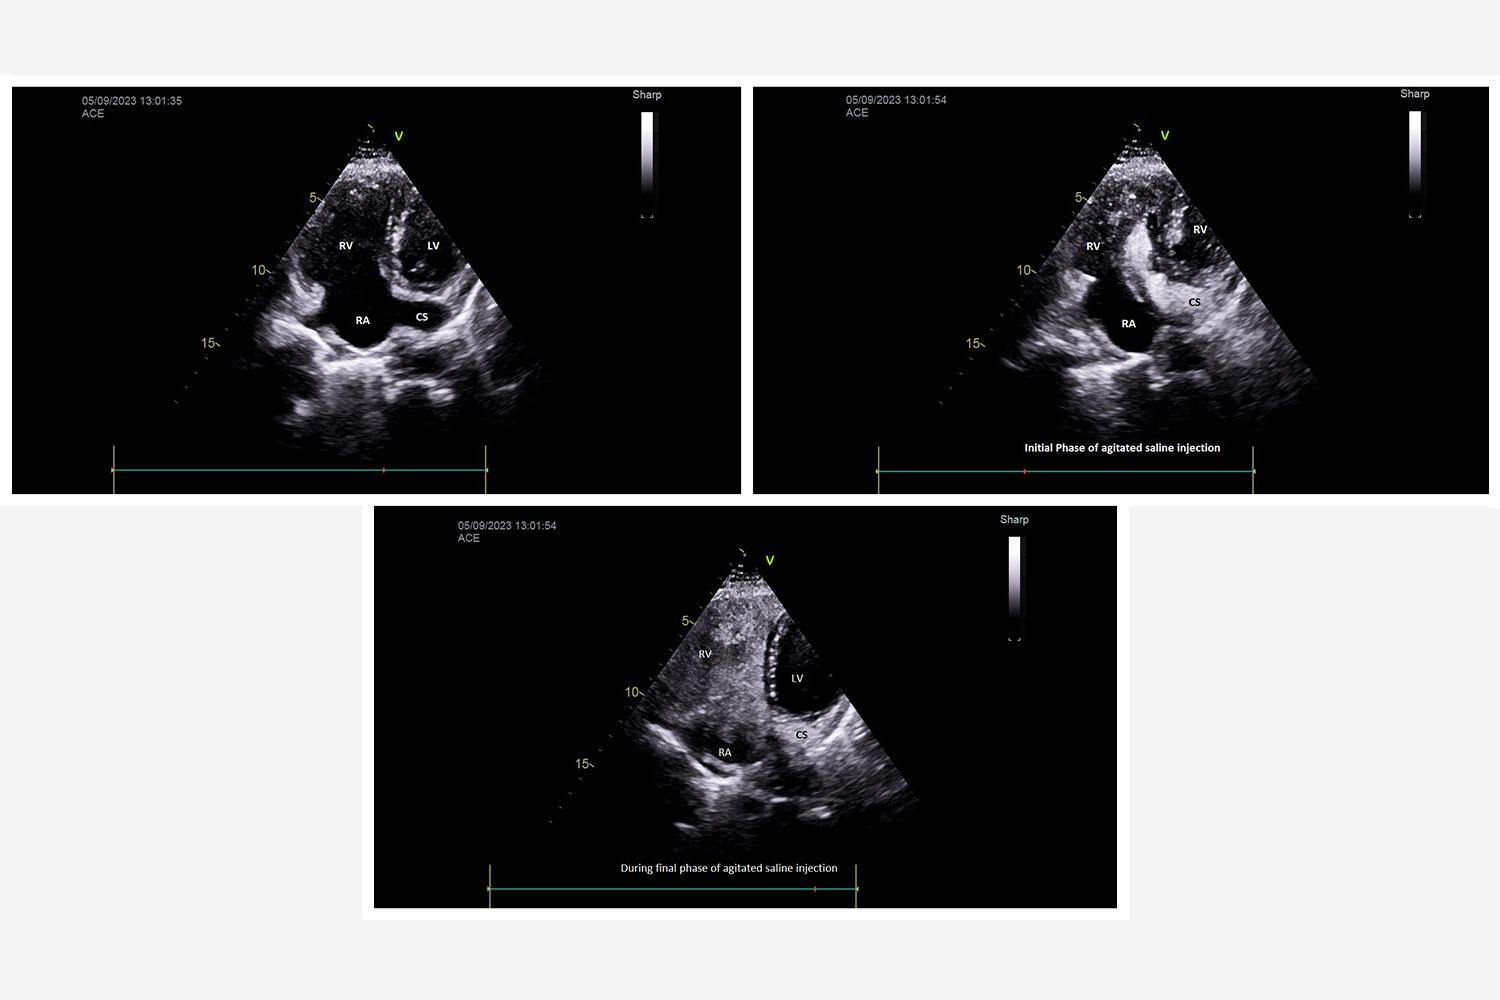

Image of the Week - 19 November 2025

Image of the week